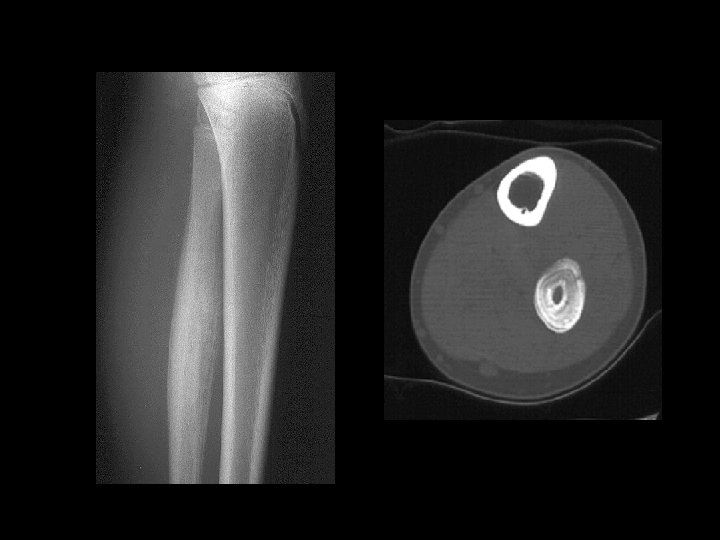

OSTEOID OSTEOMA • Small, benign, solitary painful lesion seen mainly in children & adolescents. • Any bone, tibia & femur…. . 50% Spine Painful Scoliosis

OSTEIOD OSTEOMA • Pain is the commonest presentation. • Pain is worsened by night, typically relieved by salicylates.

Example 8: 45 y/o with thigh pain

Example 8